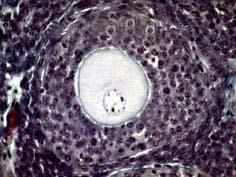

问题 如图,可将卵泡的生长过程分为以下几个阶段 ( )

选项 A、排卵前卵泡 B、卵泡闭锁 C、窦前卵泡 D、窦状卵泡 E、始基卵泡

答案 ACDE